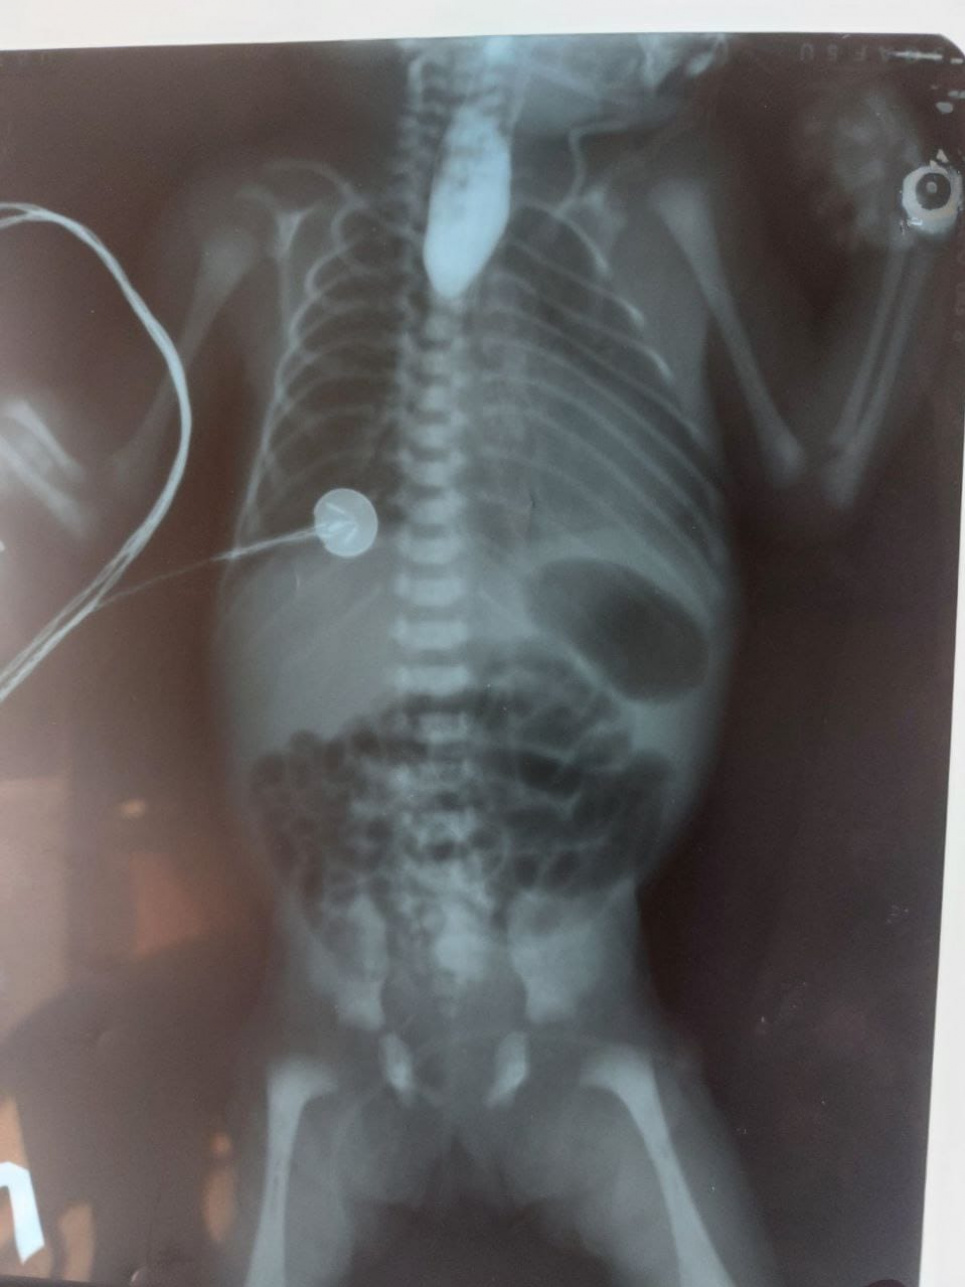

У другої дитини була відсутня частина стравоходу. Немовля народилося у дуже дуже важкому стані з масою тіла трохи більше 1 кг. Такі новонароджені з даною вадою, без оперативного лікування не мають шансів на життя. Після дообстеження та передопераційної підготовки, дитина була прооперована з формуванням нового стравоходу. Операція пройшла успішно. На сьогодні дитина продовжує своє лікування у відділені реанімації новонароджених та готуються до подальшого щасливого життя.